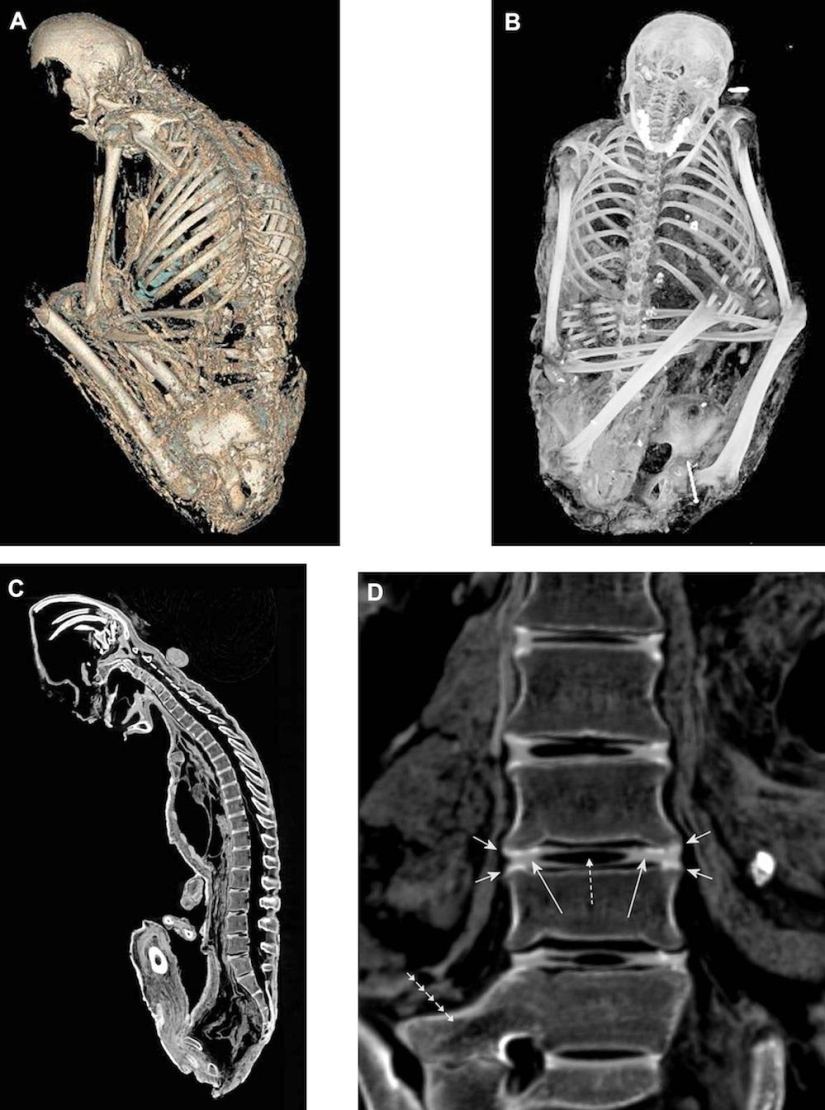

La momia de una niña de 15 años que fue sacrificada hace unos 15 años. Los científicos están casi seguros de que la niña se asfixió. Los cuerpos de tres niños sacrificados hace quinientos años están perfectamente conservados. Su cabello, piel y ADN pueden responder muchas preguntas de los científicos. Los patólogos forenses pudieron determinar exactamente cómo murieron estos niños.

Las tres momias, incluyendo esta-un niño de 7 años-se guardan en el Museo de Arqueología Alpina en Salta, Argentina.

Los científicos también llegaron a la conclusión de que los niños que se preparaban para el sacrificio, en particular una niña de 15 años, recibían regularmente drogas y alcohol para hacerlos más sumisos.

En su artículo del 29 de julio de 2013 en la revista "Proceedings of the National Academy of Sciences", los científicos concluyeron que los niños consumían regularmente hojas de coca y alcohol. Una niña de 15 años fue inyectada con la mayor cantidad de drogas en su último año de vida, y el consumo máximo de hojas de coca se produjo en los últimos seis meses de su vida.